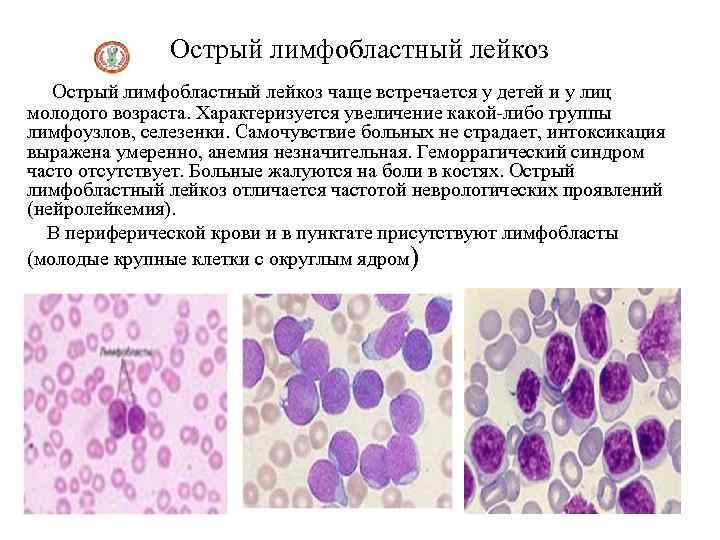

Острый лимфобластный лейкоз чаще встречается у детей и у лиц молодого возраста. Характеризуется увеличение какой-либо группы лимфоузлов, селезенки. Самочувствие больных не страдает, интоксикация выражена умеренно, анемия незначительная. Геморрагический синдром часто отсутствует. Больные жалуются на боли в костях. Острый лимфобластный лейкоз отличается частотой неврологических проявлений (нейролейкемия). В периферической крови и в пунктате присутствуют лимфобласты (молодые крупные клетки с округлым ядром)